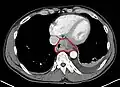

Speziell im Fall eines 3D-Datensatzes werden häufig Schnittbilder oder Schnittbildserien des Körpers errechnet. Die Orientierung der Schnittbildebene und die Position sind dabei meist frei wählbar. Im Gegensatz zu einem Projektionsverfahren wie der Durchstrahlung eines Körpers können so gezielt Details oberhalb oder unterhalb der interessierenden Schicht ausgeblendet werden. Im unteren Beispiel wurde durch die Technik der Schnittebene die störende Information der Rippen entfernt. Teilweise werden für die Diagnose oder Auswertung auch 3D-Rekonstruktionen erstellt, die sich beliebig im Raum orientieren lassen und Anblicke von allen Seiten erlauben.

-

transversales Schnittbild des Körpers